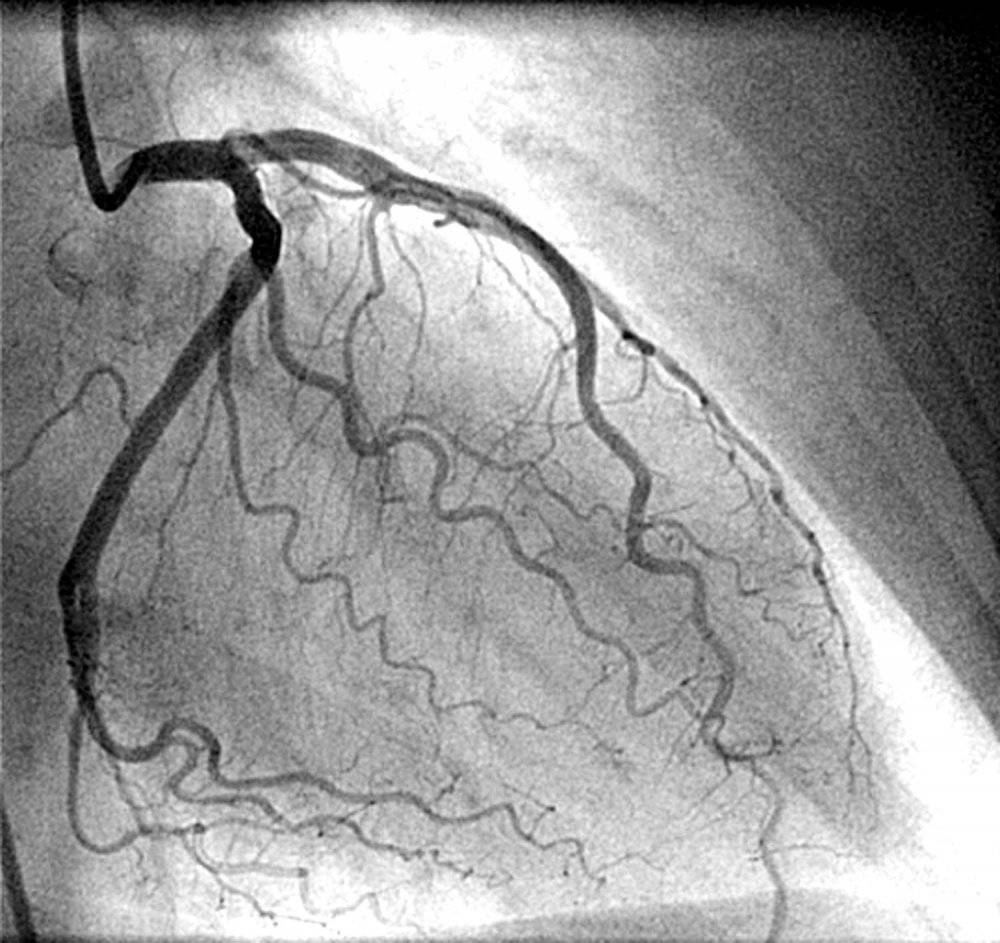

Damar sertliği tedavisinde; ilk aşamada, anjiyo denilen yansılanım yöntemi ile tıkanıklık teşhis edilir. Ardından uygulanan gayret testi ile damarın durumu belirlenir. Daha ciddi durumlarda ise bypass denilen ameliyat gerçekleştirilerek tıkalı damar açılır.